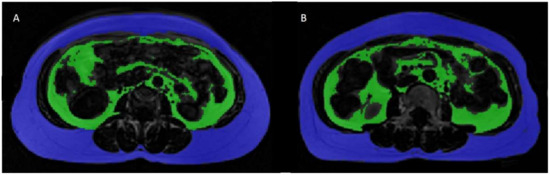

2.2. Adipose Tissue Volume Measurements

2.3. Calculation of SAT/VAT Volumes